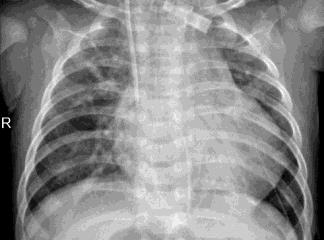

Pneumonia, a respiratory infection brought on by bacteria or viruses, affects a large number of people, especially in developing and impoverished countries where high levels of pollution, unclean living conditions, and overcrowding are frequently observed, along with insufficient medical infrastructure. Pleural effusion, a condition in which fluids fill the lung and complicate breathing, is brought on by pneumonia. Early detection of pneumonia is essential for ensuring curative care and boosting survival rates. The approach most usually used to diagnose pneumonia is chest X-ray imaging. The purpose of this work is to develop a method for the automatic diagnosis of bacterial and viral pneumonia in digital x-ray pictures. This article first presents the authors' technique, and then gives a comprehensive report on recent developments in the field of reliable diagnosis of pneumonia. In this study, here tuned a state-of-the-art deep convolutional neural network to classify plant diseases based on images and tested its performance. Deep learning architecture is compared empirically. VGG19, ResNet with 152v2, Resnext101, Seresnet152, Mobilenettv2, and DenseNet with 201 layers are among the architectures tested. Experiment data consists of two groups, sick and healthy X-ray pictures. To take appropriate action against plant diseases as soon as possible, rapid disease identification models are preferred. DenseNet201 has shown no overfitting or performance degradation in our experiments, and its accuracy tends to increase as the number of epochs increases. Further, DenseNet201 achieves state-of-the-art performance with a significantly a smaller number of parameters and within a reasonable computing time. This architecture outperforms the competition in terms of testing accuracy, scoring 95%. Each architecture was trained using Keras, using Theano as the backend.